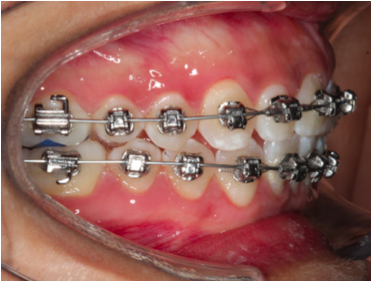

Brackets

Metálicos Transparentes Linguales Autoligado Alineadores invisibles

ortopedia maxilar y ortodoncia

Si tengo un TRATAMIENTO MAL HECHO

Si te atiendes con un dentista que no es especialista y las cosas van mal...